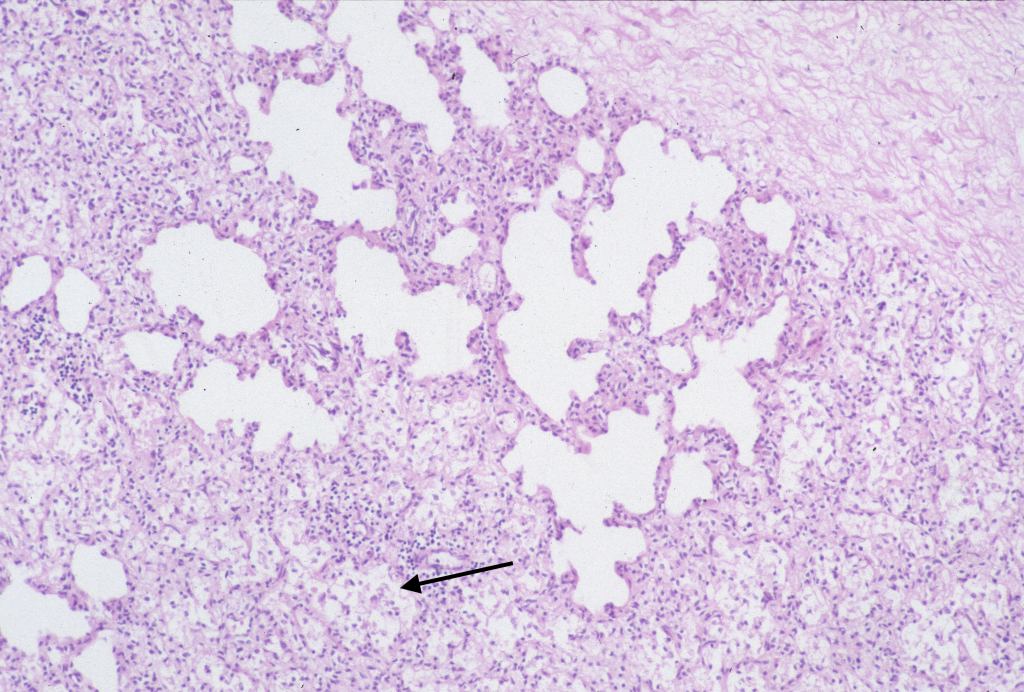

Pulmonary hypoplasia microscopic: With standard sections of the lung, pulmonary hypoplasia may demonstrate smaller lobules and a sheared appearance of the parenchyma compared to similarly sectioned gestationally matched controls (Fig 26). Radial alveolar counts can quantify that appearance by counting the septa crossed by a straight line from the most distal bronchiole to the pleural surface and comparing to expected numbers at gestation18.